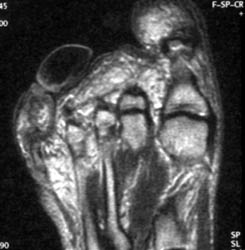

55 years old male with slowly growing mass at the tip of the plantar aspect of 4th toe. Plain films demonstrate well defined non-calcified mass at the tip of plantar aspect of 4th toe. MR imaging demonstrates this mass has low to intermediate signal intensity on all the sequences.